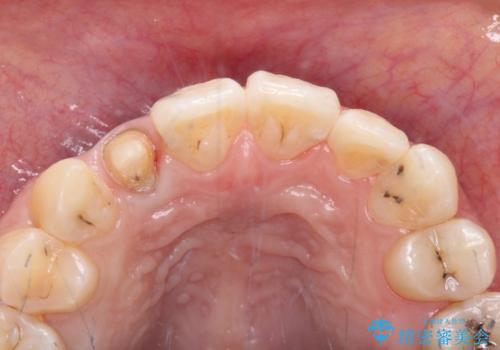

以前治療した前歯をきれいに治したい オールセラミッククラウン

- 根管治療はやり直さずに、ファイバーポストを使用した土台を植立して、オールセラミッククラウンにて補綴することとしました。

神経を取り除いた歯の変色は、クリーニングやホワイトニングでは改善できないため、オールセラミッククラウンなどによる補綴治療が必要となります。